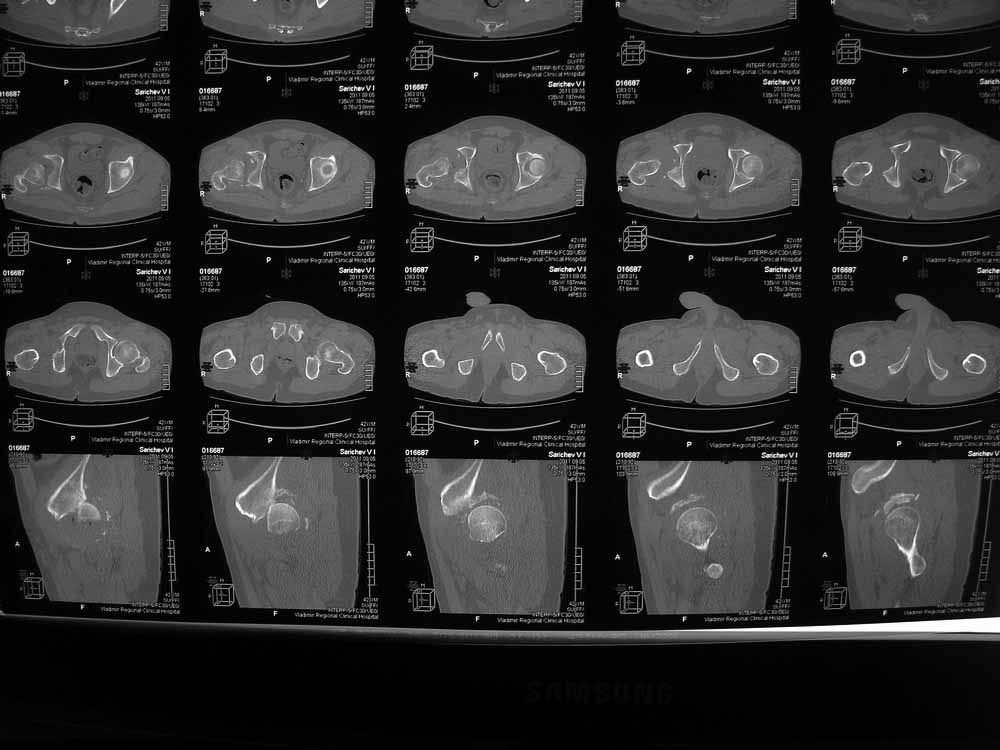

Re: Застарелый вывих бера, перелом вертлужнойвпадины, перелом головки бедра

Вот еще сканы.